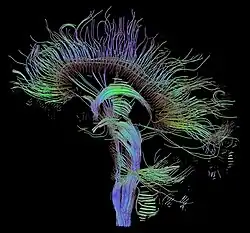

Diffusion-weighted magnetic resonance imaging (DWI or DW-MRI) is the use of specific MRI sequences as well as software that generates images from the resulting data that uses the diffusion of water molecules to generate contrast in MR images.[1][2][3] It allows the mapping of the diffusion process of molecules, mainly water, in biological tissues, in vivo and non-invasively. Molecular diffusion in tissues is not random, but reflects interactions with many obstacles, such as macromolecules, fibers, and membranes. Water molecule diffusion patterns can therefore reveal microscopic details about tissue architecture, either normal or in a diseased state. A special kind of DWI, diffusion tensor imaging (DTI), has been used extensively to map white matter tractography in the brain.

The principal application is in the imaging of white matter where the location, orientation, and anisotropy of the tracts can be measured. The architecture of the axons in parallel bundles, and their myelin sheaths, facilitate the diffusion of the water molecules preferentially along their main direction. Such preferentially oriented diffusion is called anisotropic diffusion.

The imaging of this property is an extension of diffusion MRI. If a series of diffusion gradients (i.e. magnetic field variations in the MRI magnet) are applied that can determine at least 3 directional vectors (use of 6 different gradients is the minimum and additional gradients improve the accuracy for "off-diagonal" information), it is possible to calculate, for each voxel, a tensor (i.e. a symmetric positive definite 3×3 matrix) that describes the 3-dimensional shape of diffusion. The fiber direction is indicated by the tensor's main eigenvector. This vector can be color-coded, yielding a cartography of the tracts' position and direction (red for left-right, blue for superior-inferior, and green for anterior-posterior).[45] The brightness is weighted by the fractional anisotropy which is a scalar measure of the degree of anisotropy in a given voxel. Mean diffusivity (MD) or trace is a scalar measure of the total diffusion within a voxel. These measures are commonly used clinically to localize white matter lesions that do not show up on other forms of clinical MRI.[46]

- Diffusion tensor imaging data can be used to perform tractography within white matter. Fiber tracking algorithms can be used to track a fiber along its whole length (e.g. the corticospinal tract, through which the motor information transit from the motor cortex to the spinal cord and the peripheral nerves). Tractography is a useful tool for measuring deficits in white matter, such as in aging. Its estimation of fiber orientation and strength is increasingly accurate, and it has widespread potential implications in the fields of cognitive neuroscience and neurobiology.